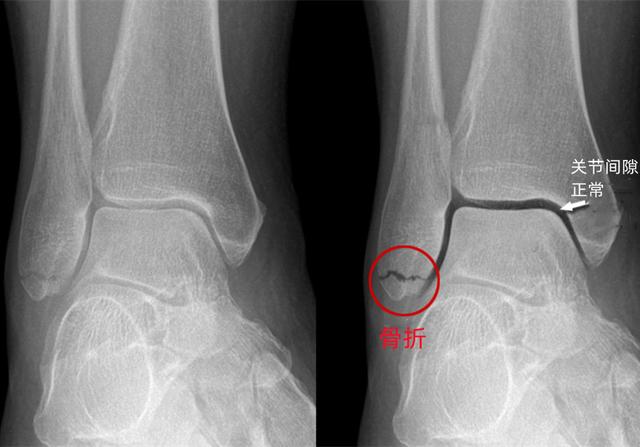

X光和CT都能看骨头,该用哪一个,哪些人不适合?